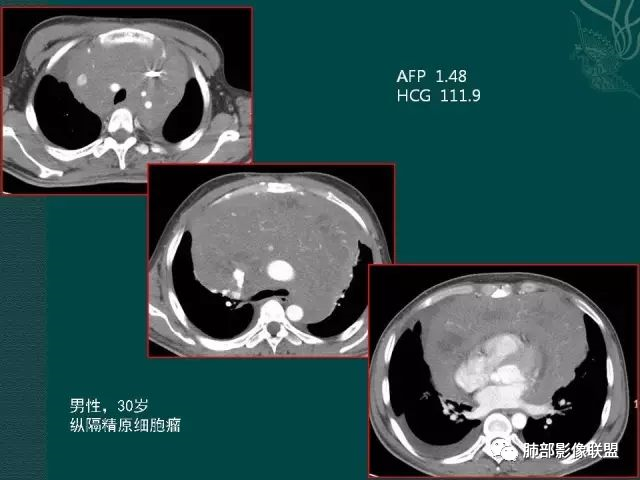

精原细胞瘤

临床缺乏特异性,几乎见于男性,一般血清LDH升高,部分β-HCG轻度升高,精原细胞瘤不产生AFP,血AFP升高可考虑非精原细胞瘤或混合生殖细胞肿瘤。影像表现一般肿块巨大,分叶状,边界不清,可浸润性生长,无钙化及脂肪,有纤维分隔,轻中度强化,易转移。

男性,32岁,精原细胞瘤